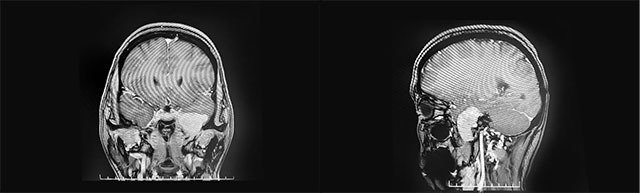

▲ 肿瘤位于左侧颅中窝颞叶内侧底部

头颅MRI平扫+增强显示:左侧颅中窝颞叶内侧底部见一肿块影,矢横高径约3*4*3cm,边缘尚清晰,形态不规则(局部向左侧桥小脑角略凸起),毗邻左侧颞叶、桥脑脑组织受压内移,增强扫描显著明显强化(向左侧桥小脑角凸起灶环状强化)。